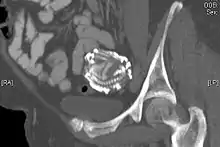

A CT scan showing an extra-uterine calcified foetal skeleton, a lithopedion